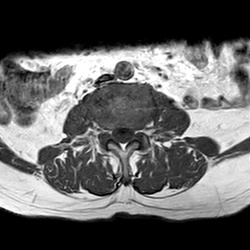

MRI_eeAX_T1W_Lumbal_902

25 photos